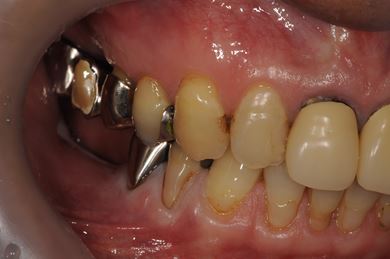

インプラントの症例写真 IMPLANT

| 性別/年齢 | 男性 / 61歳 | ||||||||||||||||||||||||||||||||

| 主訴 | 奥歯のインプラント治療を希望。 | ||||||||||||||||||||||||||||||||

| 治療内容 | インプラント4本、メタルボンドセラミッククラウン4本 | ||||||||||||||||||||||||||||||||